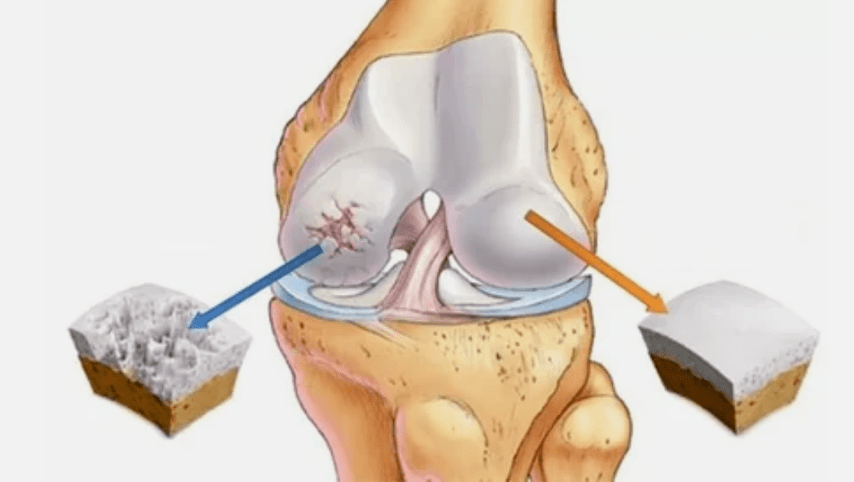

- The main lesion affects the cartilage of hyaline.When blood circulatory violations, the deterioration of pathological power occurs.The first step or reason that arthrosis may occur.

- Hyaline coating pathologies.The tenderness of the cartilage leads to changing his pathological tissues - bone structures.

- The cartilage appears in anomalous growth - osteophytes.

- The violation of the natural anatomy of cartilage and bones provokes excessive loading of the healthy areas of the cartilage.The destruction of articular tissues without treatment is constantly progressing and causes disability.

When the degree of disease increases, pathological processes are still aggravated.In the end, the cartilage of the whole hyalen was destroyed.